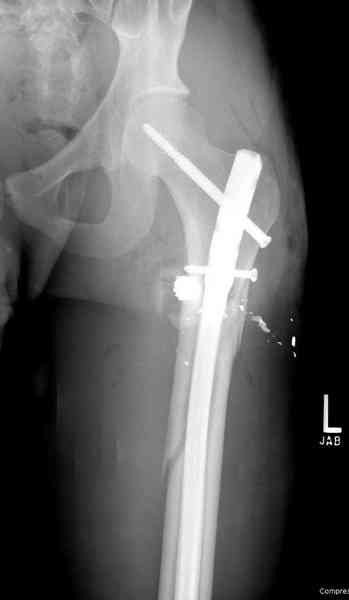

В нашем случае 21 летний боец уличного фронта, фиксацию провели на следующий день, зафиксирован интрамедуллярным штифтом. Не стали делать первичную хирургическую обработку точечной раны, зафиксирован как есть. Клинические снимки: